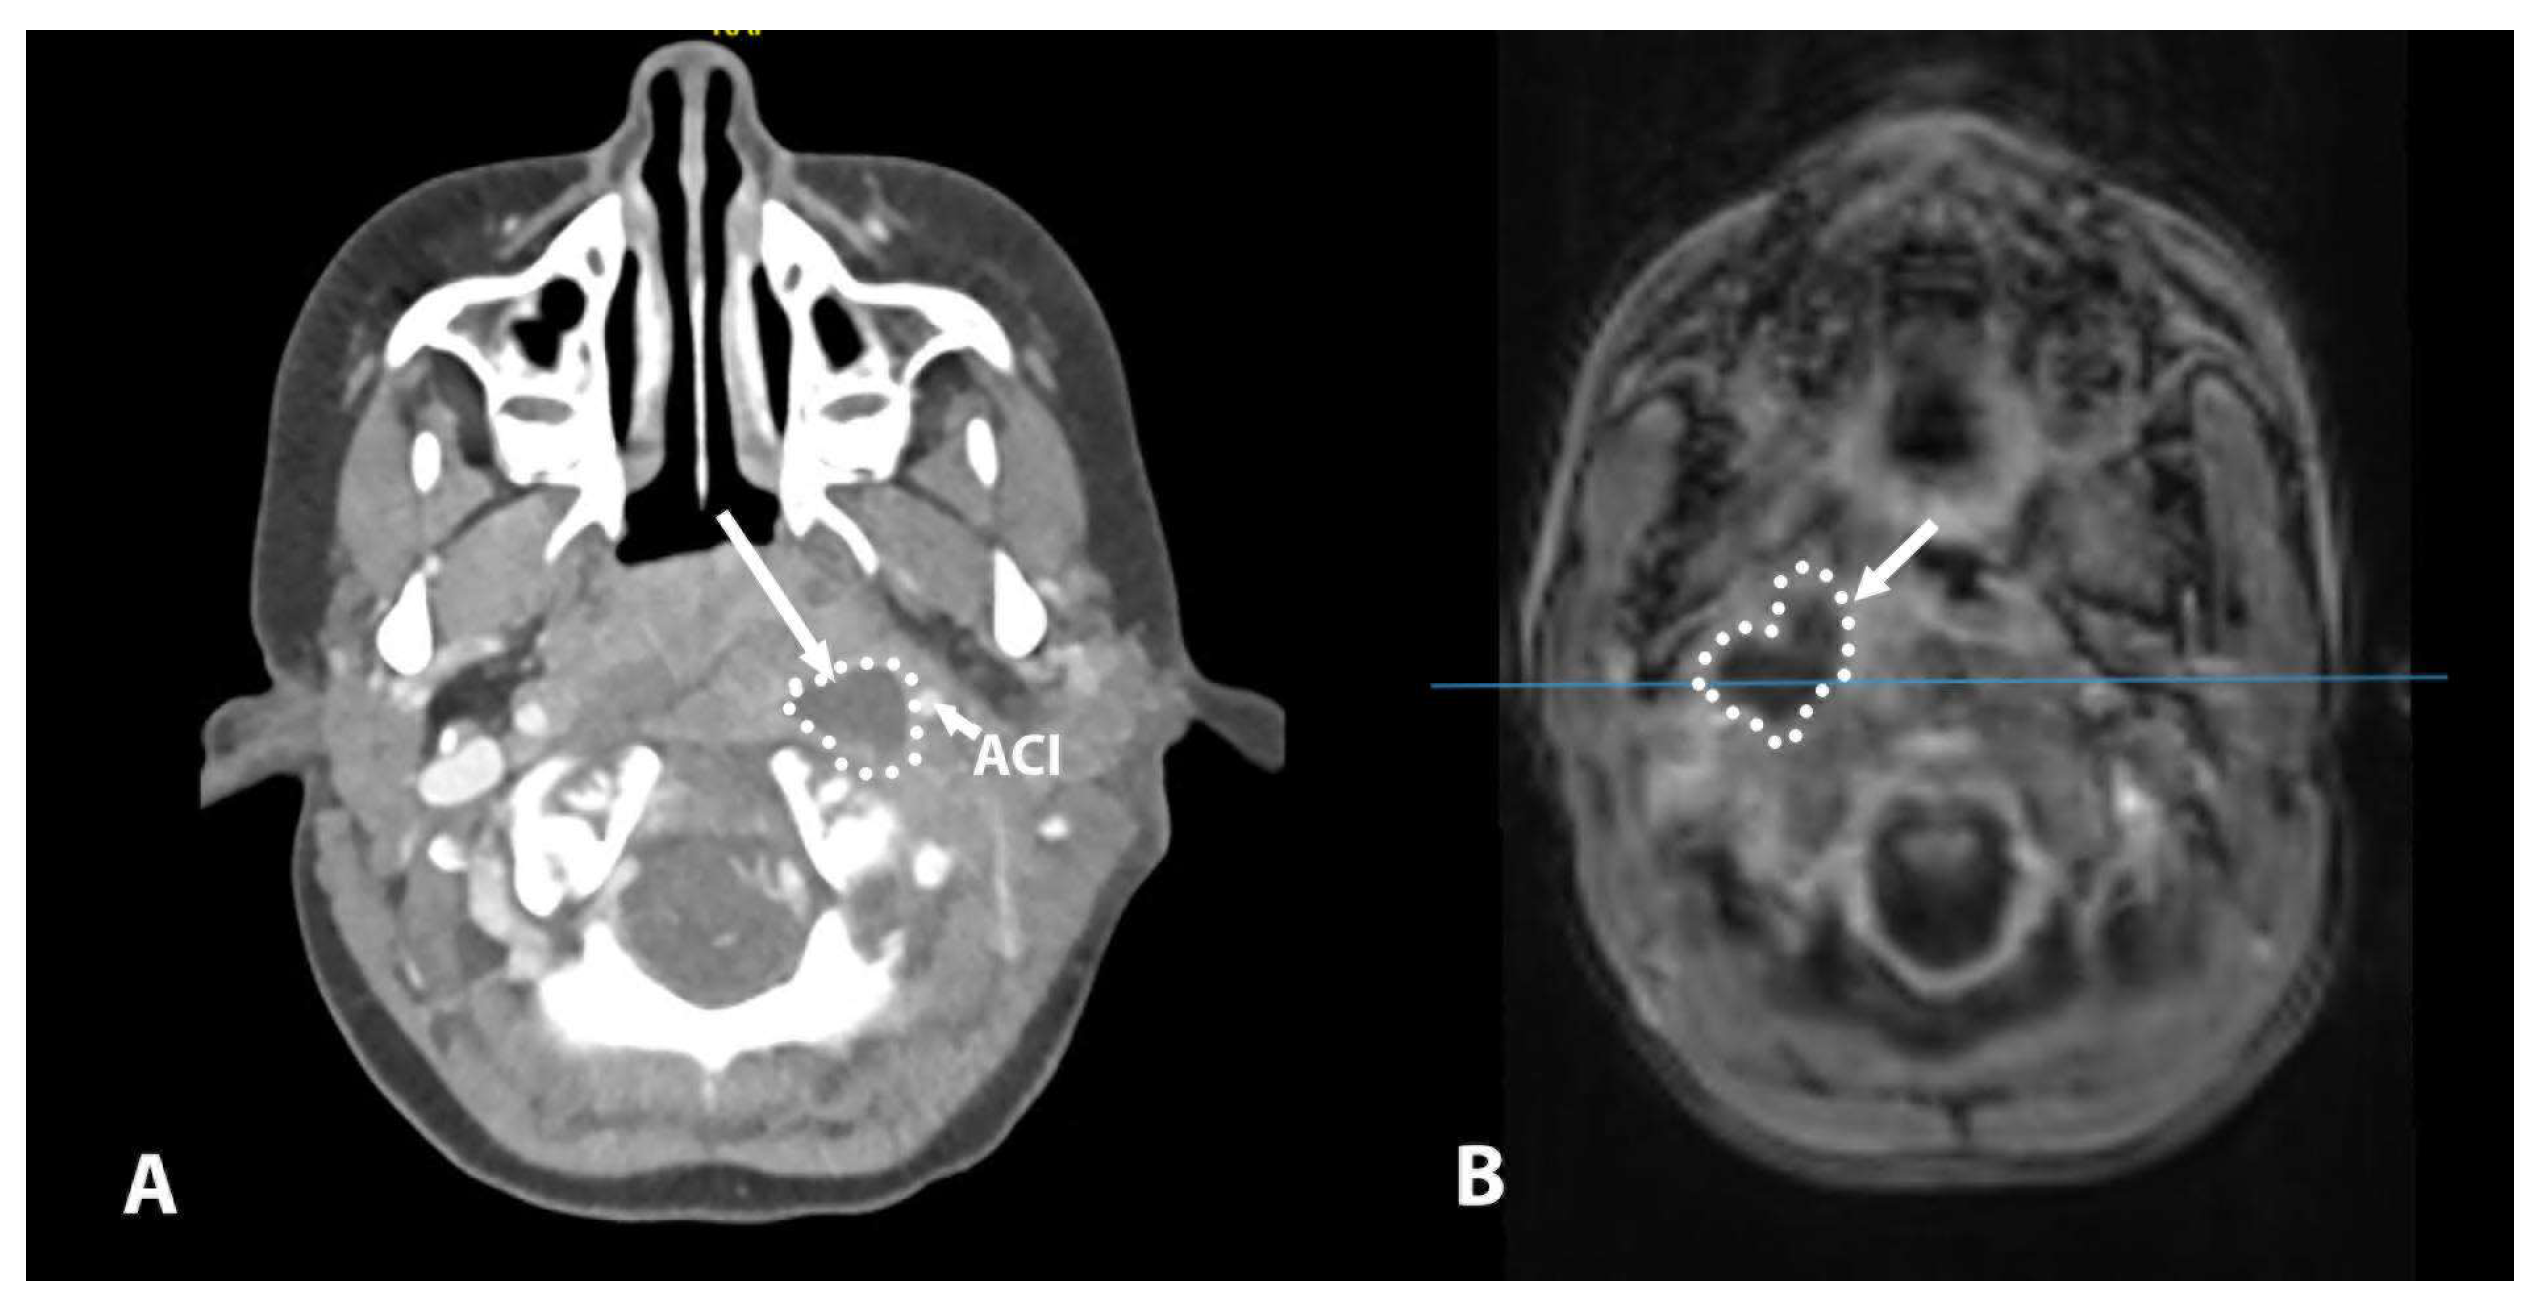

| 6 | 3 years | Parapharyngeal | Conglomerate of enlarged level II lymph nodes, area of collection in level II lateral to ICA | Major parapharyngeal collection 53 × 25 × 45, lateral and anterior to ICA | / | Intubation | Lateral | CT |